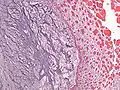

Micrograph of an atrial myxoma. H&E stain. | |